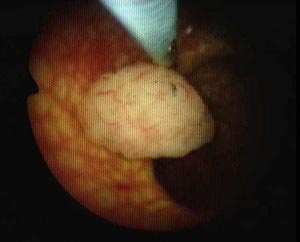

人流费用推荐治疗技术——新式内镜微创保胆取息肉术

襄阳第三人民医院无痛人流诊疗中心采用新式内镜微创保胆取息肉术治疗人流费用,除了体现保留胆囊功能的微创精神外,还体现了切口小,创伤轻,恢复快,美容佳,费用少,无复发的特点,深受广大患者的欢迎。 该技术属于一种微创外科手术,是现代高科技与传统外科技术结合的产物。它最大的优点是没有传统意义上的腹部手术切口,避免了因手术切口带来的种种损伤和不适。

新式内镜微创保胆取息肉术技术特点:

1、干净彻底:在取净息肉的同时,完整保留患者的胆囊和胆囊功能;

2、创伤更小:整个手术微创、可视、安全系数高,让患者和家人都放心。

3、效果好,恢复快:一般在术后6~8小时可下床活动,最快1.5小时即可下床,术后第一天就可进食流汁。经适当输液、抗炎治疗两天,术后3~4天即可出院。